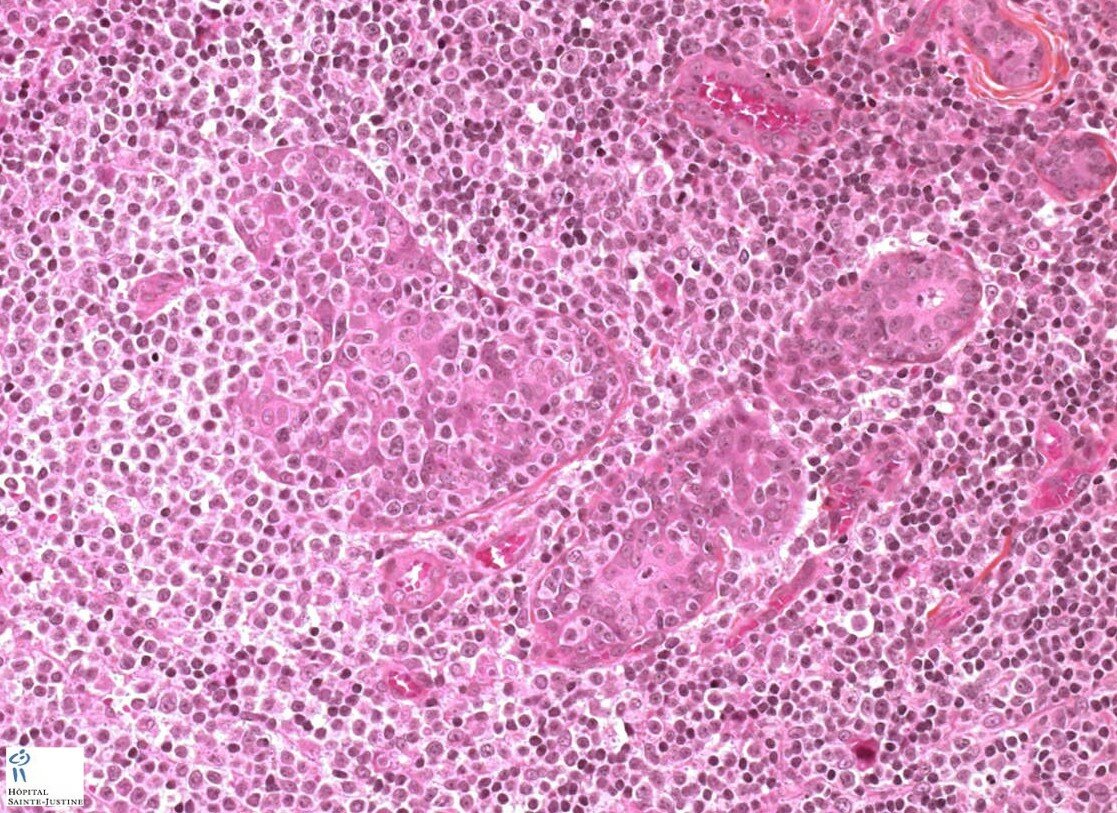

Atypical salivary lymphoid hyperplasia